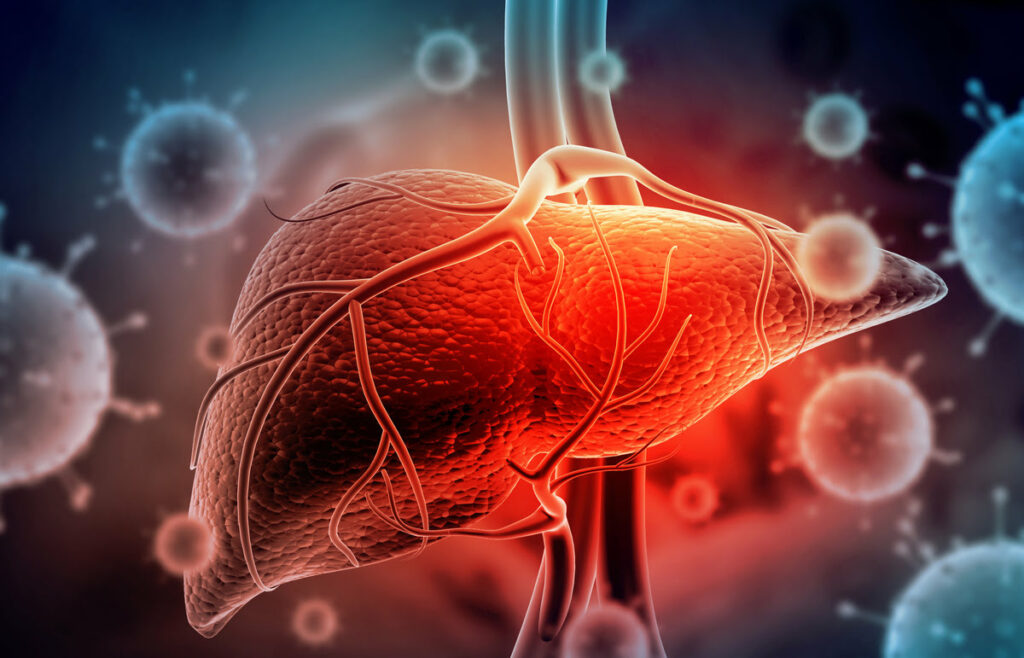

Les chercheurs continuent d’observer les conséquences du virus du Covid sur l’organisme. Le virus peut infecter les cellules du foie et provoquer une maladie proche du diabète.

Les personnes touchées par un Covid long ou récemment infectées le savent : le Covid est encore présent. Les chercheurs aussi continuent d’étudier les effets du virus sur le corps humain. Une équipe brésilienne, dont les travaux sont publiés dans la revue PNAS, met en lumière l’action du virus du Covid sur les cellules du foie. L’étude a été menée auprès de 269 patients en soins intensifs et de 663 patients admis avec suspicion de Covid-19 au Centre de médecine intensive (CEPETI) entre mars et août 2020.

Le virus du Covid provoque une hyperglycémie

«Le Sars-CoV-2 provoque directement l’hyperglycémie, indépendamment de l’utilisation de corticoïdes, du stress dû à l’hospitalisation, du poids corporel et du diabète», a déclaré Luiz Osório Silveira Leiria. Elle est coauteure de l’étude, chercheurs à la Fondation de recherche de São Paulo (Brésil). Toute personne infectée par le Covid peut ainsi souffrir d’une hyperglycémie, alors même qu’elle n’était pas diabétique avant.

Une hyperglycémie «nocive» chez les personnes déjà diabétiques

Le chercheurs brésiliens soulignent que cette hyperglycémie est particulièrement «nocive chez les personnes déjà diabétiques avant l’infection» font remarquer les scientifiques. En effet, en cas de diabète, le foie n’arrive plus à réguler la glycémie, le taux de sucre dans le sang. En « relâchant » trop de sucre dans le sang, le foie d’une personne diabétique provoque déjà une hyperglycémie.